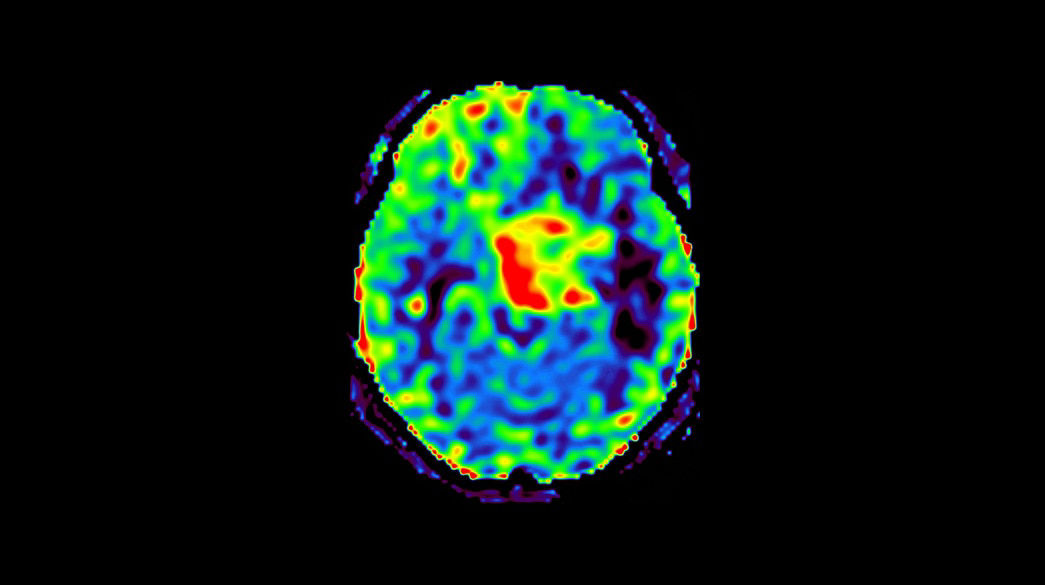

Quantifiable

Provides quantitative and actionable information